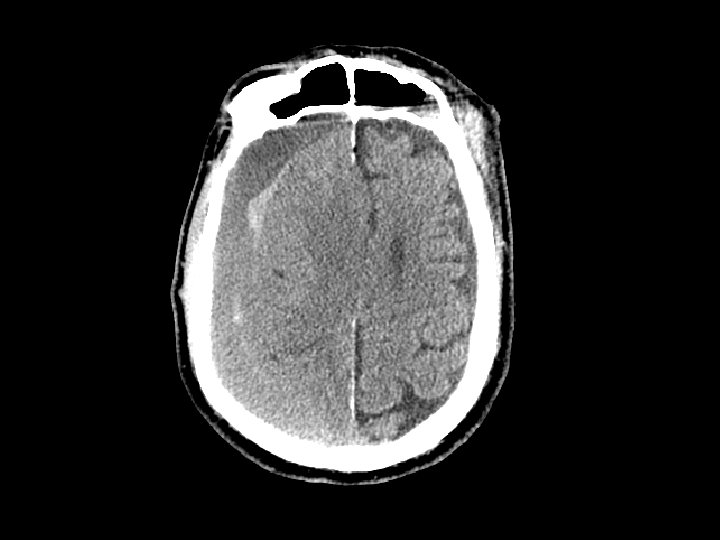

Subdural Hematoma (SDH) • Hemorrhage between the dura and the brain – More common than EDH – 30% of patients with TBI have a SDH • CT: Crescent shaped area of blood • Can be acute, subacute or chronic – Subacute or chronic presents days/weeks after injury

Subdural Hematoma (SDH) • Elderly at risk (less severe mechanisms) – Brain shrinks with age resulting in stretching of the bridging veins in the subdural space • May gradually enlarge (slower than EDH) • Surgical drainage for lesions resulting in masse effect and shift

Intracerebral Hematoma • Similar to cerebral contusions – More severe type injury – Bleeding within the brain itself • Frontal and temporal lobes • Close observation for progression of bleeding • May cause mass effect that results in herniation